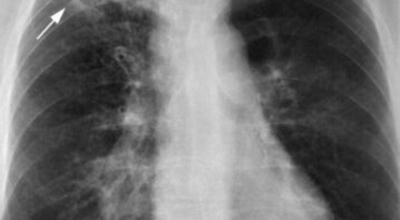

흉부 엑스레이

엑스레이 검사 방법으로는 실제 크기로 촬영하는 흉부 직접 촬영과 마이너스 70mm, 100mm 사진으로 촬영하는 간접 촬영이 있다고 하며, 일부 사람을 단체로 검사할 때 간접 촬영이 많이 활용돼요. 조사결과에 근거하면 결핵은 과감염성 결핵과 재활성성 결핵으로 구분되며, 기존 결핵은 소아결핵과 성인결핵으로 소속되는 경우가 많았어요. 인간면역결핍바이러스(HIV)에 감염된 사람들은 주로 과감염된 결핵을 보이 다고 알려져 있답니다.